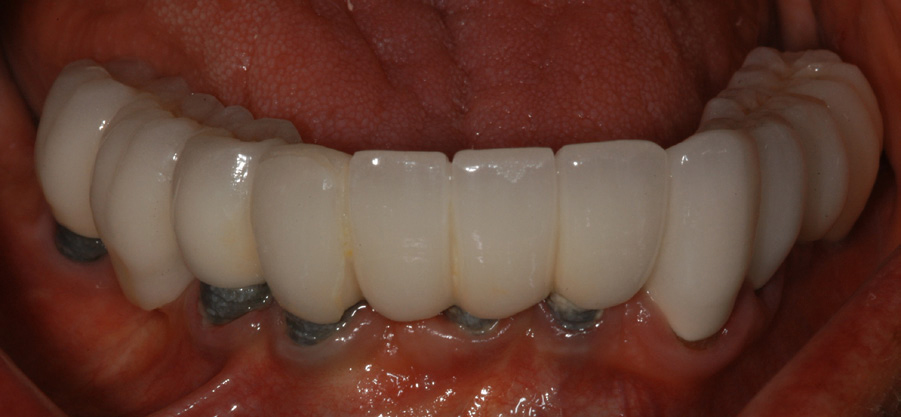

RESTORATIVE PROTOCOL

A restorative temporization procedure immediately follows implant placement surgery. Often times, especially in the esthetic zone, immediate abutments are placed over the implant to support an immediate, temporary restoration.

After 4 to 6 months of tissue healing and osseointegration, the final restoration is fabricated. An impression is obtained, either at implant level or at the abutment level, to fabricate the final crown. The implant-level impression records the implant position and requires precision. An impression coping is screwed onto the implant to be transferred into the impression. The copings are utilized for a closed- or open-tray technique. The closed-tray technique is used mostly with one implant, and the open-tray technique is used more frequently for multiple implants, when different implant angles exist (Figure 31 and Figure 32). With either technique, the impression material most often recommended is polyether.38 Bite registration, shade selection, and opposing models are collected in the same manner as crown-and-bridge cases.

There are different types, shapes, and sizes of abutments that are either prefabricated by the manufacturer or custom crafted by a dental laboratory technologist (Figure 33). The choice of abutment is made according to the esthetics desired, the thickness of the tissue around the implant, and the angle of the implant. It is important to note that every abutment is connected to the implant using a screw.

The crown can be cemented into place or retained by a screw over the implant. For a multiple-implant bridge or bar overdenture restoration, the framework try-in appointment is important prior to porcelain build-up or overdenture fabrication to ensure a passive fit. The fit must be confirmed by a radiograph. Framework trial appointments require a minimal setup. No anesthetic is required; however, a screwdriver for the chosen implant system is required.

The implant prosthesis delivery appointment is similar to that of a crown or bridge delivery (Figure 34). If the prosthesis is screw-retained, then no cement is necessary and an occlusal filling material, such as composite, is necessary. After the occlusal bite registration is checked, the patient receives home care instructions regarding restoration maintenance (Figure 35).

Figure 34 – Metal-free fixed partial denture cemented on the abutments.

Figure 34